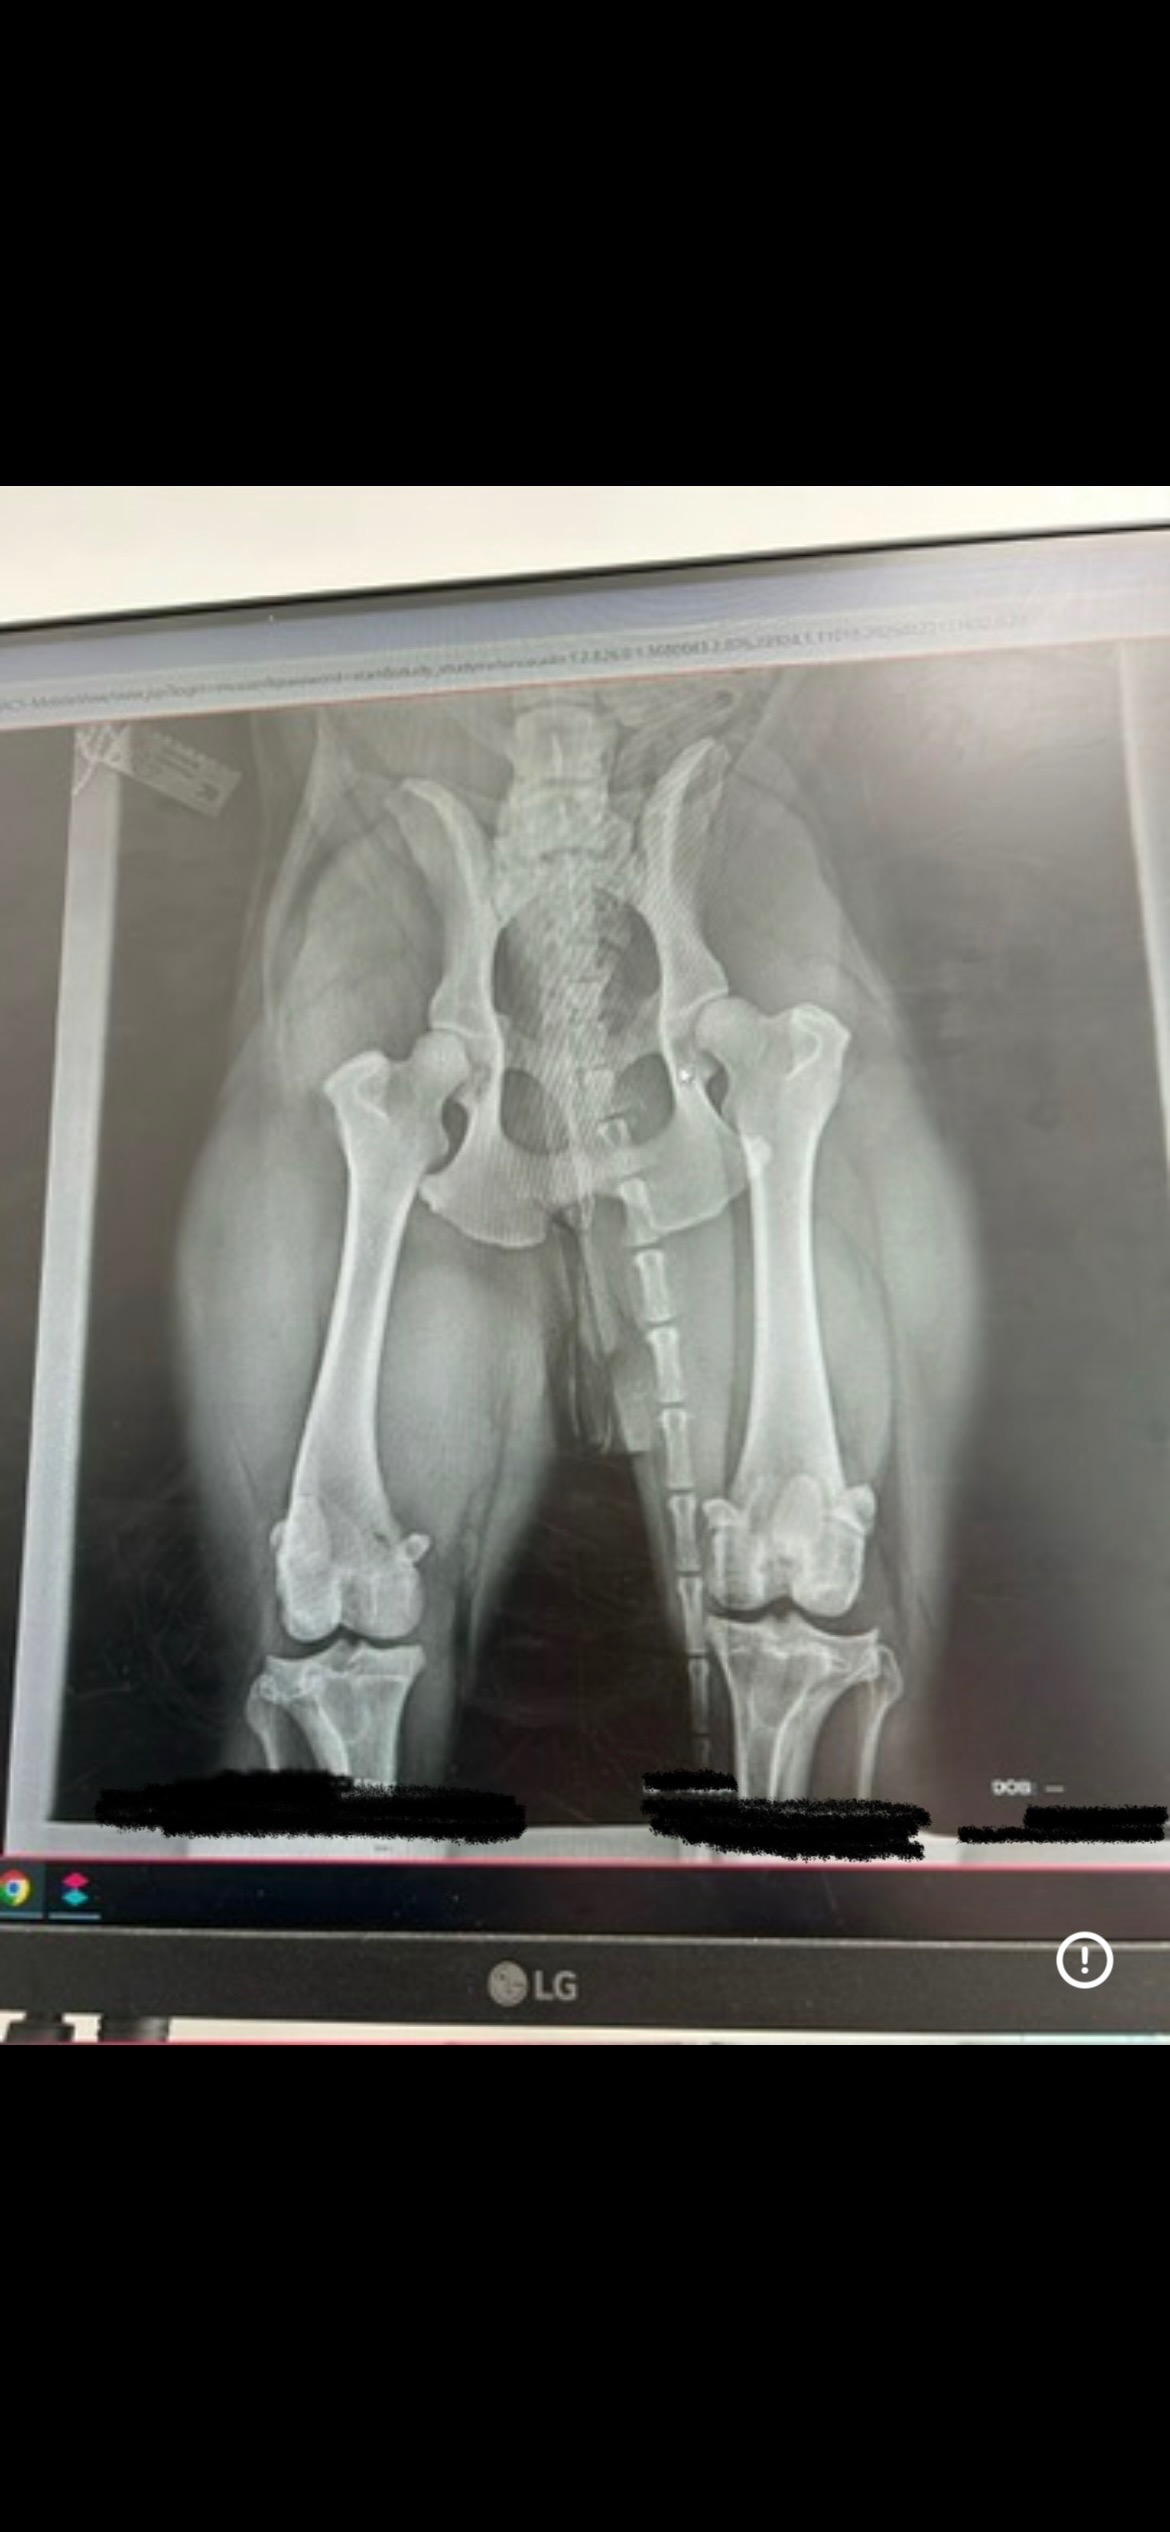

I have hip dysplasia and osteoarthritis, and my x-rays showed that the ligament in my left back leg is torn. The vets said that without TPLO surgery, I will never be able to walk properly again.